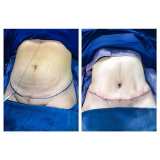

Você precisa de um consultório médico que realize abdominoplastia com lipo com segurança!

Agende uma visita e converse com toda a equipe. Ela está sempre pronta a atendê-lo! O objetivo é priorizar o tratamento adequado aos pacientes. A FF Cirurgia Plástica tem compromisso com a vida.